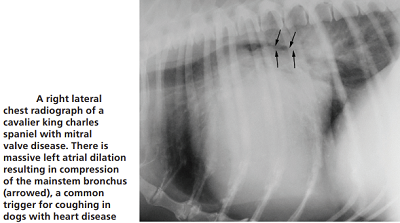

• coughing is not a symptom of CHF

Most MVD-affected dogs with a cough are not yet in heart

failure. However, many veterinarians associate a dry, hacking cough with an enlarged

heart due to MVD or even to heart failure. They call it a "cardiac

cough" and attribute it to either the enlarged left atrium conpresising

against the dog's bronchus or trachea (see photo at right), or, fluid build-up in the lungs due to CHF

(pulmonary edema). In most all cases, however, the term cardiac cough is

a misnoner because the true cause of the cough probably is respiratory

related and completely independent of any heart disorder.

The cough could be due to a combination of factors, which include the enlarged left atrium of the heart pressing against and compressing the left mainstem bronchus or trachea, but more likely to airway disorders independent of any relationship with the heart, such as bronchomalacia and airway inflammation (possibly with the large left atrium merely highlighting the bronchial narrowing). It may even cause the trachea to collapse*. However, if the dog coughs up a pink-tinged fluid, it would indicate that may have very severe pulmonary edema which is filling the airways.

In a January 2019 article, a pair of experts concluded that a cough in the absence of rapid and labored breathing would indicate that it is due mainly to a respiratory disease rather than a cardiac disease. Coughing is a hallmark sign of bronchitis. Dogs with severe pulmonary edema can cough, but coughing is much more common with primary lung disease. By severe pulmonary edema, they mean that the fluid has completely filled the lungs and also has started to fill the upper airway passages, as well. (The x-ray below shows the heart's enlarged left atrium impinging upon the left main bronchus.).